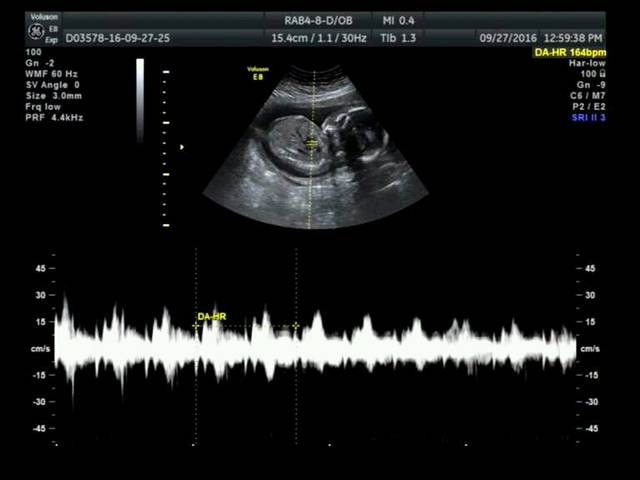

16周+3天b超图,看得出男宝还是女宝吗?医生说是男宝,但是老公说医生语气不肯定,说宝宝腿蛮长的_育儿问答_宝宝树

400x400 - 15KB - JPEG